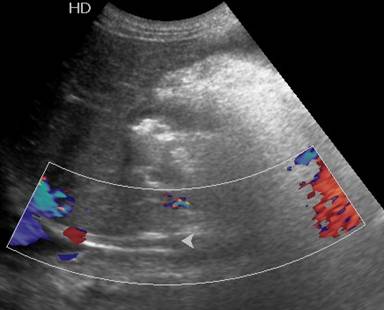

A 30-year-old man presented to our outpatient clinic with history of abdominal distention without pedal edema for the past 3 months. He also had deep boring epigastric pain and vomiting for 2 months. He had noticed low grade fever and anorexia for last 15 days. He had been consuming alcohol (100 g/day) for last 5 years (last drink 3 months back). Examination revealed pallor, facial puffiness, tachycardia, ascites and bilateral pleural effusion. His neck veins were engorged and hepatojugular reflex was absent. On investigation ascitic fluid was hemorrhagic with proteins 5.5 g/dL (reference range: 0-0.5 g/dL); white blood cells were 215 mm-3 (reference range: 0-5 mm-3; polymorphs 35% and lymphocytes 65% in a background of red blood cells). Ascitic fluid adenosine deaminase was 20 IU/mL (reference range: 0-35 IU/mL) and ascetic fluid amylase 58,840 IU/L (reference range: 0-100 IU/L). Pleural fluid was also hemorrhagic with protein 5.5 g/dL (reference range: 0-0.5 g/dL), white blood cells 80 mm-3 (polymorphs 50%, lymphocytes 50%) and adenosine deaminase was 35 IU /mL. 2D echo was normal. Serum amylase was 700 IU/L (reference range: 0-150 IU/L), serum lipase was 3,526 IU/L (reference range: 0-150 IU/L), and pleural fluid amylase was 5,748 IU/L (reference range: 0-50 IU/L). CT scan showed thromboses of bilateral subclavian and internal jugular vein, superior vena cava, infra renal inferior vena cava, a segment of suprarenal and infrahepatic inferior vena cava and right common iliac vein and patent splanchnic veins (Figures 1-5). Color Doppler abdomen showed normal portal vein of 10 mm diameter with hepatopetal flow, normal retrohepatic inferior vena cava with hepatopetal flow, while rest of inferior vena cava was thrombosed; all three hepatic veins well visualized with normal flow (Figure 6). MRCP revealed acute inflammation with underlying chronic pancreatitis with stricture at junction of head and body with intraductal calculi with leak at head and body junction and multiple loculated intra abdominal collections. The prothrombotic work up, including factor V Leiden, JAK 2 mutation, homocysteine, antiphospholipid antibody, protein C and S, and antithrombin III, was negative. Thus, a diagnosis of chronic pancreatitis with pancreatic ascites and pleural effusion with multiple extrasplanchnic thromboses due to pancreatitis was made. Patient was managed conservatively with intravenous heparin, initially continuous infusion of 1,000 units/hour and later on oral anticoagulants. ERCP with pancreatic sphincterotomy was done and a 5Fr x 10 cm stent was placed. Patient symptomatically improved with complete disappearance of ascites. His repeat color Doppler showed partial recanalization of superior vena cava, internal jugular vein and subclavian veins (Figure 7).

Figure 6. Color Doppler image shows thrombosed infra hepatic segment of inferior vena cava. |

|